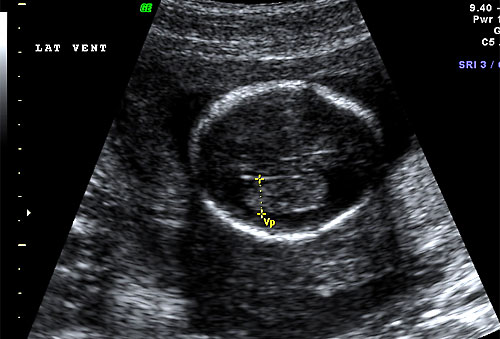

Normal 16 week ventricular atria (lateral ventricle size) |

Normal 16 week bilateral ventricles |